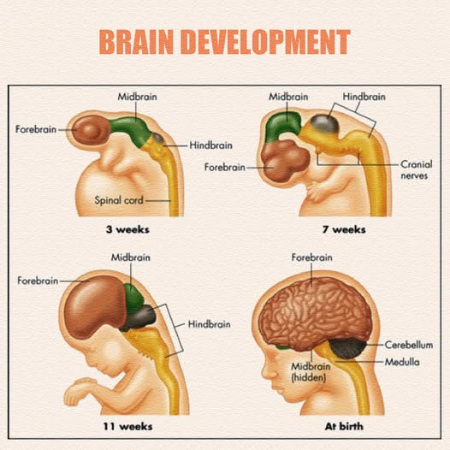

تحقیقات پیشرفته در سالهای اخیر نشان میدهد که گام نخست زایمان غالباً از سوی جنین برداشته میشود. جنین زمانی که احساس میکند بدن و اندامهای حیاتیاش برای زندگی خارج از رحم به بلوغ رسیدهاند، شروع به ترشح هورمونهایی میکند که مستقیماً بر جفت و سپس رحم مادر تأثیر میگذارند.

نمیتوان تصور کرد که جنین آگاهانه تصمیم میگیرد متولد شود، اما سیستم عصبی و هورمونی او این «محاسبه» را بهصورت بیولوژیک انجام میدهد. چند عامل مهم در این تصمیمگیری دخالت دارند:

۱. بلوغ ریهها و تولید سورفاکتانت

زمانی که ریههای جنین در حال تکامل هستند، مادهای به نام سورفاکتانت ترشح میشود. این ماده علاوه بر کمک به عملکرد ریهها، مولکولهایی تولید میکند که به جفت پیام میدهند زمان زایمان نزدیک است.

برخی پژوهشها نشان دادهاند که این پیامها از عوامل اصلی تحریک زایمان هستند.

جنین زمانی فرمان تولد را صادر میکند که ریهها و دیگر اندامهای حیاتیاش به بلوغ نزدیک شده باشند. معمولاً این فرآیند در حوالی هفتههای ۳۸ تا ۴۰ بارداری رخ میدهد، اما بسته به شرایط، کمی زودتر یا دیرتر هم ممکن است.

جنین آگاهی ذهنی ندارد، اما سیستم عصبی و هورمونیاش شرایط آمادگی را «تشخیص» میدهد. زمانی که ریهها و اندامها به تکامل نزدیک میشوند، پیامهای هورمونی بهطور خودکار فعال میشوند و این همان چیزی است که ما به آن «فرمان جنین برای تولد» میگوییم.